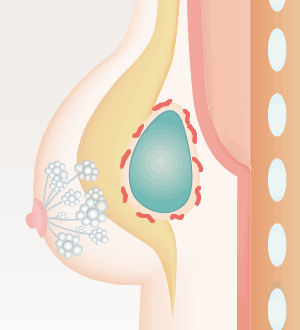

多くの場合、ヒアルロン酸を注入すると体は異物が入ってきたと捉えるので、コラーゲン線維の被膜で閉じ込めようとします。しかし、これは正常な生体反応。通常なら、被膜の薄いうちに体内の酵素成分がヒアルロン酸を分解、吸収されてなくなります。しかし、何らかの理由で分解されるより前に厚い被膜ができてしまった場合、しこりとして残ってしまうのです。

- しこりになる場合

- ヒアルロン酸の周囲に

被膜を形成

- 分解・吸収されることなく残留